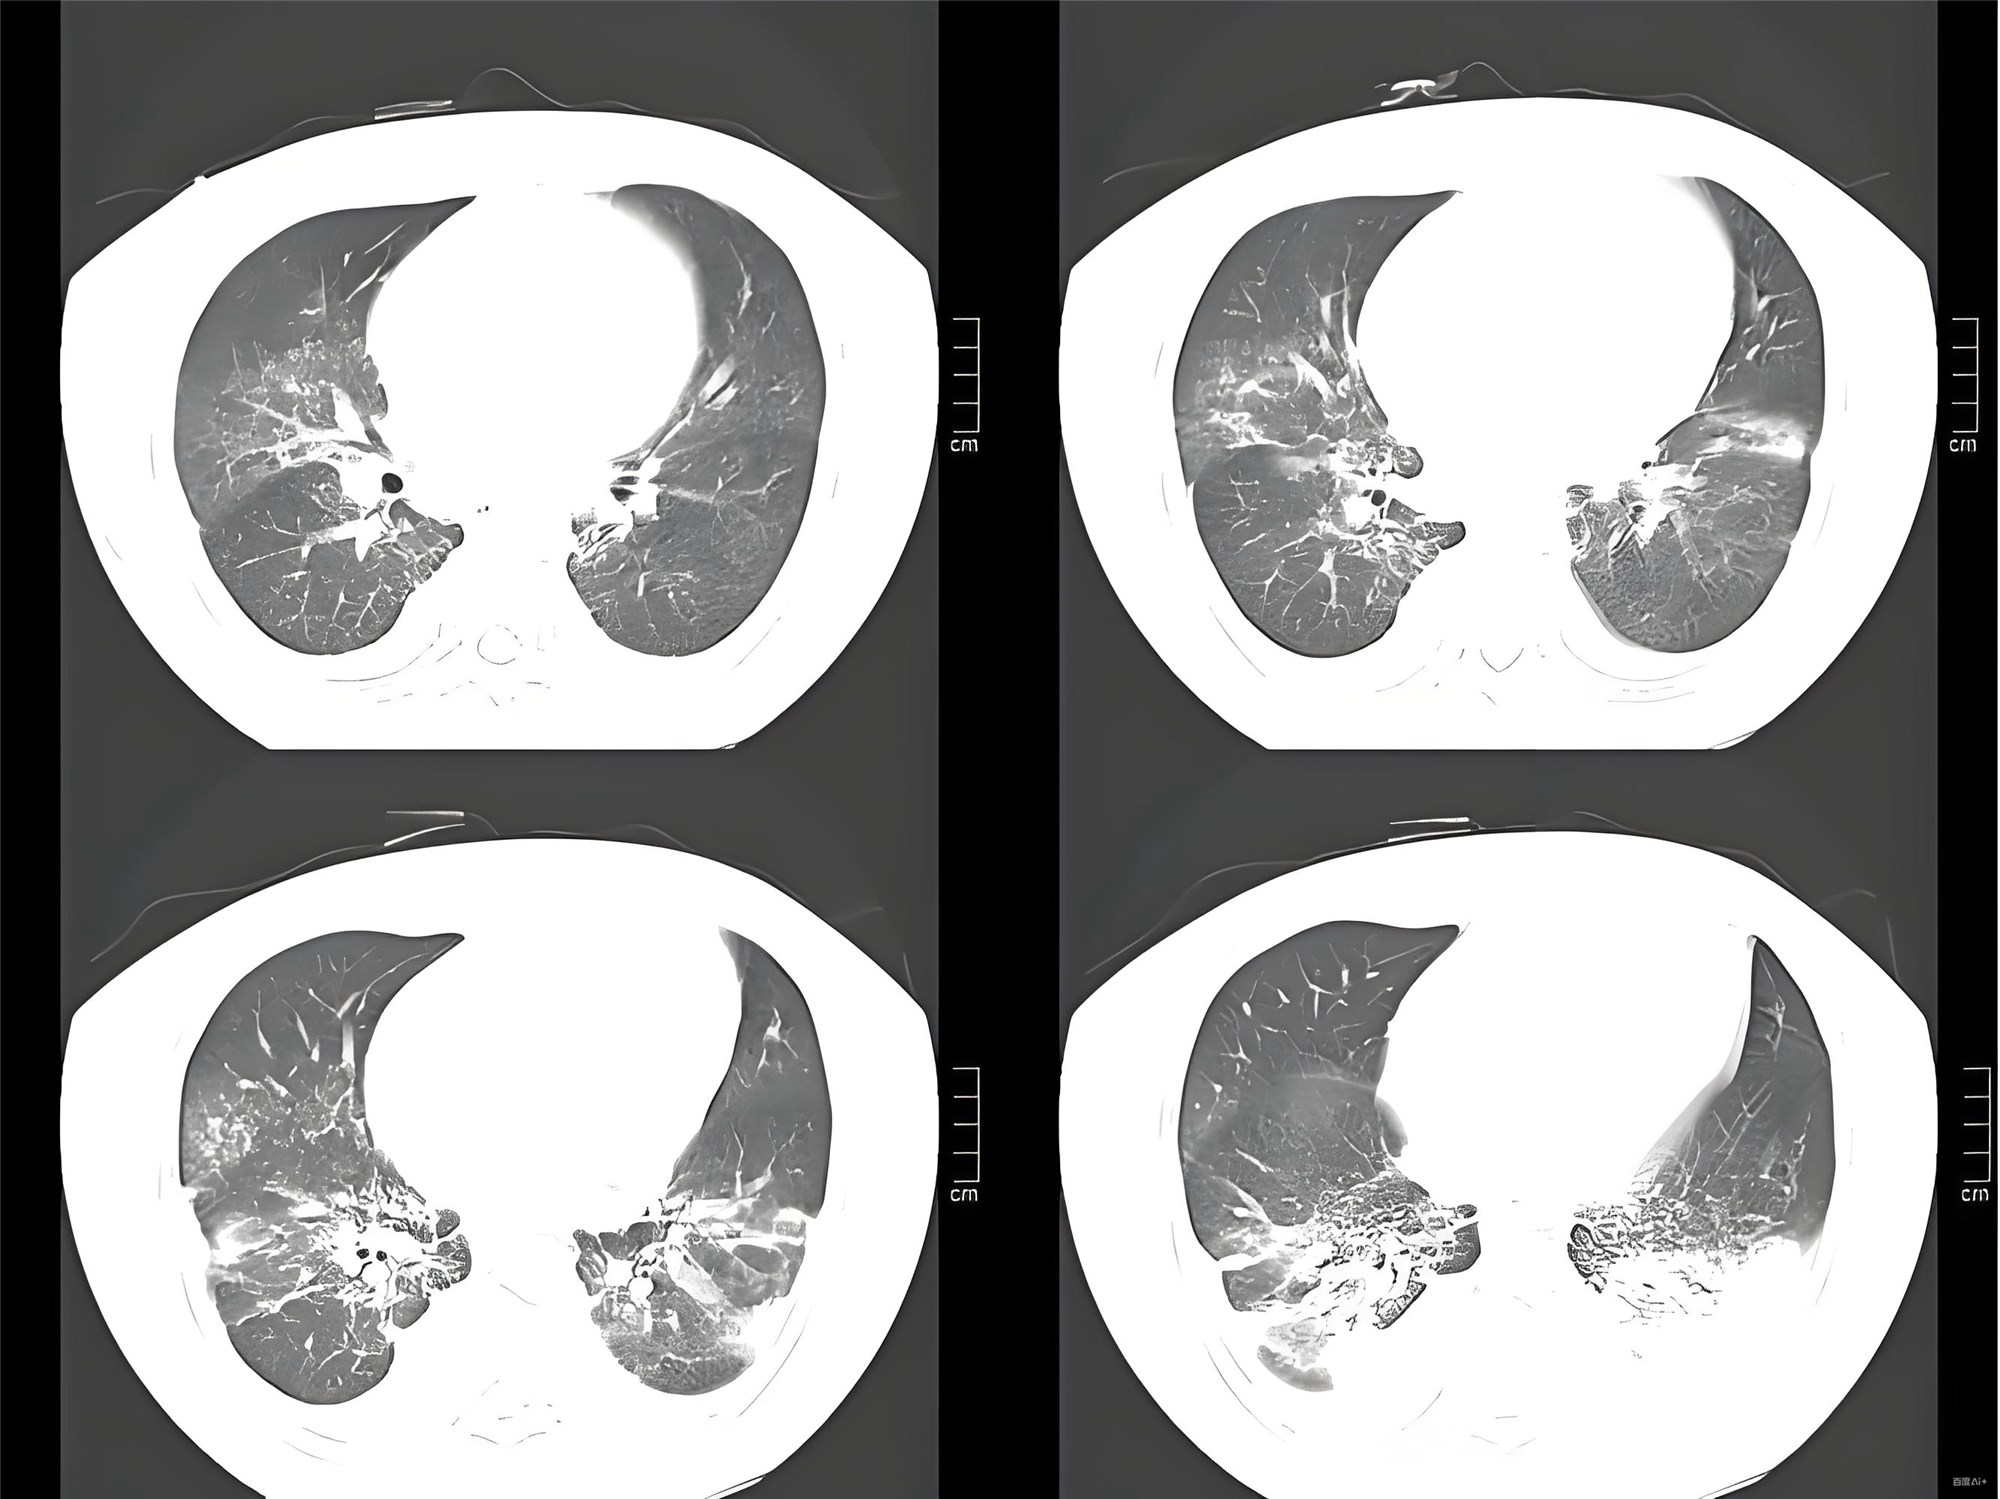

- 胸部CT示右下肺实变伴支气管充气征

- 影像学:右下肺实变(典型吸入性肺炎定位)

- 推荐低剂量胸部CT(敏感性更高)+快速分子病原检测